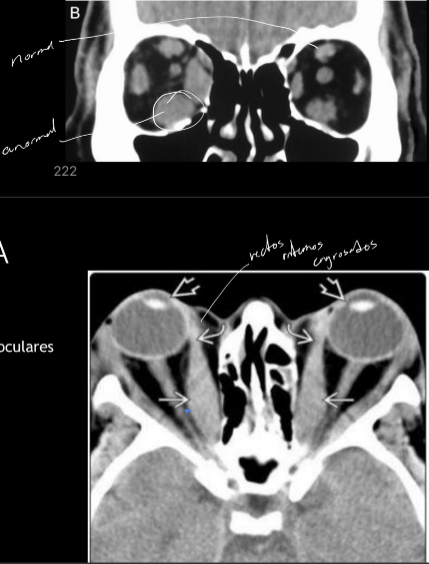

Tc exoftalmos

A

TC

- protusion ocular anormal

- disociacion indice globo ocular

RM exoftalmos

RM

- disociacion indice globo ocular - linea intercantal

- masa ocupativas retroculares

Estudio imagen Orbitopatia tiroidea

Agrandamiento bilateral de musc extraoculares

- TC: abordar enf no complicada

- RM: decidir tx y ver compromiso del n.optico